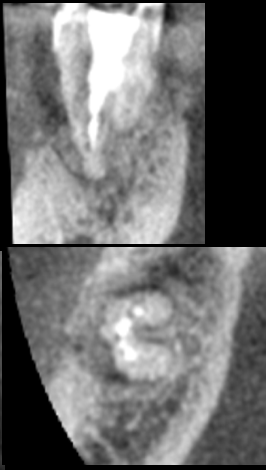

上唇の腫脹を認め、CT検査にて根尖部に嚢胞様透過像を認めた。左上の前歯が不自然に大きく噛み合わせが強くなっていたことがフレアアップの一因と考える。精密根管治療を行い、感染経路を遮断したのち歯根端切除術にて嚢胞を摘出した。

治療前